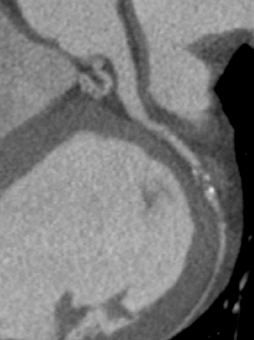

a. 心臓CT

SPECT/CT融合画像

図3 労作性狭心症症例。後側壁〜後下壁の心筋虚血はLCXおよびRCA両方の有意狭窄による。